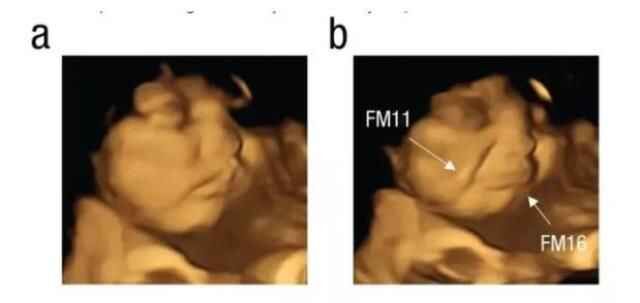

Independent'ın haberine göre, Durham Üniversitesi'nden bilim insanları, fetüslerin farklı tatlara tepki verip vermediğini görmek için 4D ultrason taramaları kullandı. Durham Üniversitesi Psikoloji Bölümü'den Beyza Üstün'ün liderliğindeki araştırma ekibi, fetüslerin belirli tatları ayırt edip edemediğini görmek için 18-40 yaşları arasındaki 70 hamileyi iki gruba ayırıp ultrason görüntülerini inceledi.

Psychological Journal'da yayımlanan çalışmada araştırmacılar, annenin diyetinden gelen tat ve koku bileşimli aromaların 32 ila 36'ncı gebelik haftalarında amniyotik sıvıda hissedildiğini tespit etti.

LAHANA TATINI ALINCA YÜZÜNÜ EKŞİTTİ

Çalışmaya katılan anne adaylarının raporlama öncesinde herhangi bir gıda tüketmemesi talep edildi. Çalışma kapsamında bir grup anne toz havuç tüketirken diğer grup ise lahana tozu yedi. Lahana tozuna maruz kalan bebeğin, yüzünü ekşittiği görüldü. Fetüslerin reaksiyonunu doğumdan önce gösteren ilk çalışma olarak nitelendirilirken makalede imzası olan Dr. Benoist Schaal da sonuçların bu kadar net olmasını şaşırtıcı olarak değerlendirdi.